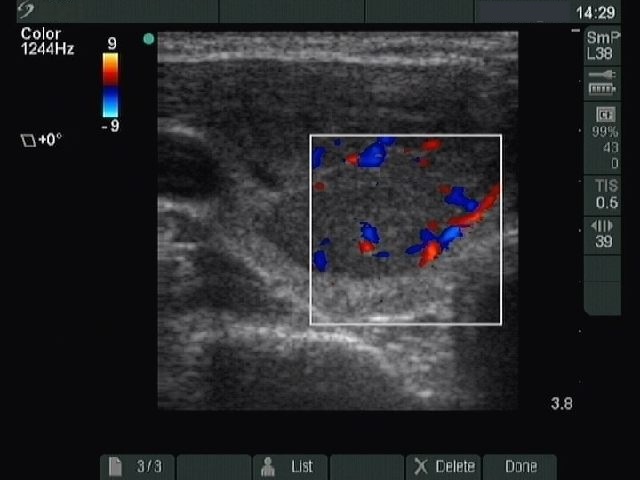

Ultrasonography: a solitary hypoechogenic nodule in the right lobe.